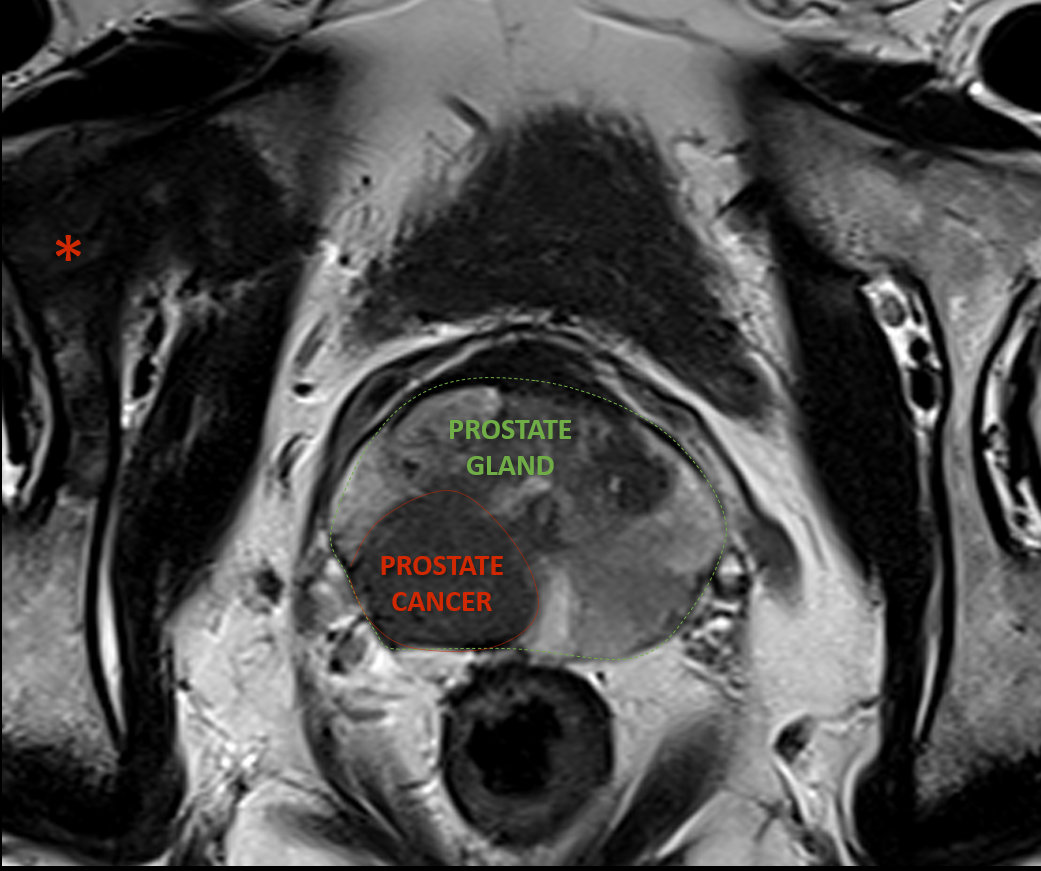

For individuals facing other cancer risks, understanding survival prospects can be crucial. For example, men concerned about their prostate removal life expectancy often seek detailed information on the outcomes and longevity after such surgery.